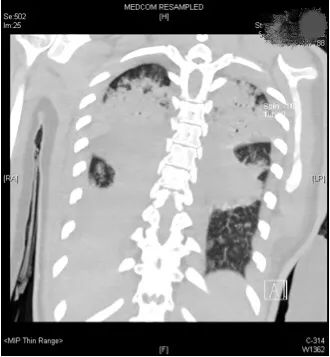

58fb3fc374e44e8d67914c3dbab64164.jpg

小文的影像检查

经过专家全面评估后,结果不容乐观,呼吸机的支持水平要求很高,100%纯氧条件下小文体内的氧分压才勉强达标,持续高烧超过40摄氏度,CT复查提示两肺几乎全部实变,炎症指标非常高。